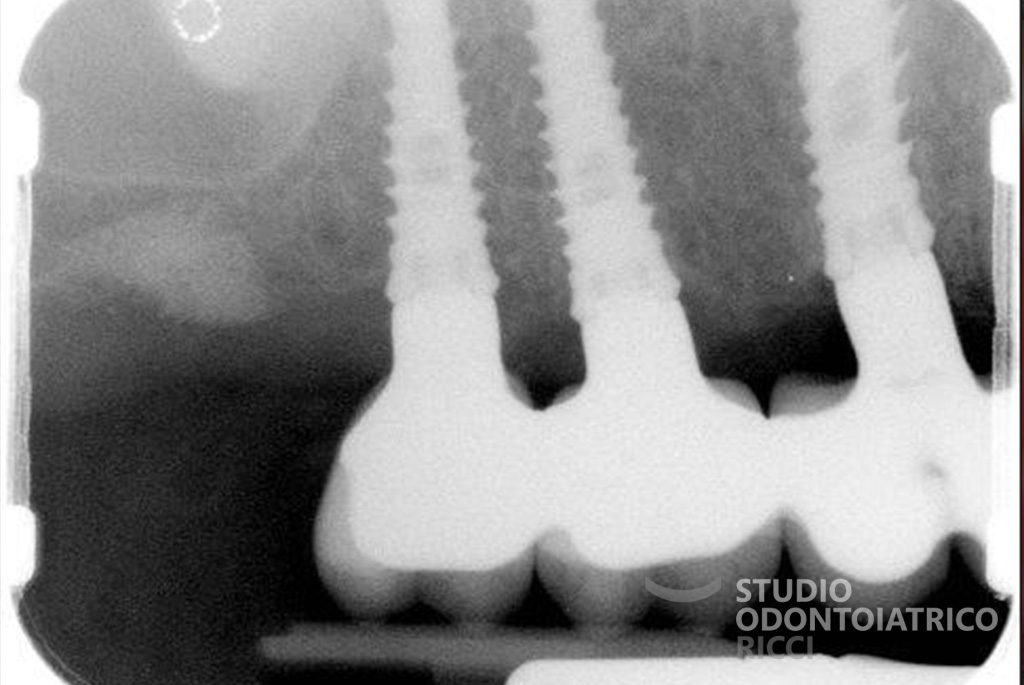

Gli impianti sono radici artificiali in titanio biocompatibile, inserite nell’osso mascellare tramite un intervento chirurgico mini-invasivo, eseguito in anestesia locale.

La maggior parte dei pazienti può sottoporsi a un trattamento implantare. È però fondamentale eseguire uno studio preliminare, con esami radiografici (es. TAC) per valutare:

quantità e qualità dell’osso